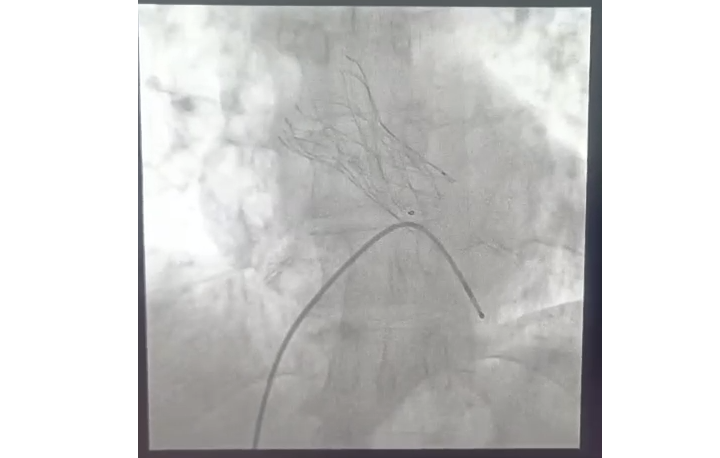

• Angiography